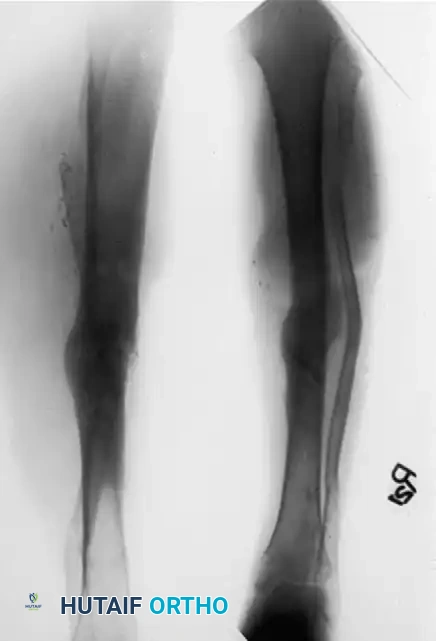

For hypertrophic nonunions with minimal infection and no sequestered bone, monofocal compression is utilized. The inherent biology of a hypertrophic nonunion is excellent; it simply lacks mechanical stability. Compression via the Ilizarov frame provides rigid stability and stimulates the existing fibrocartilage to ossify.

Conversely, atrophic nonunions with diffuse infection or sequestered bone require a bifocal approach. Open resection of the infected, necrotic segment is performed until healthy, bleeding bone is reached.

If the soft tissue envelope is poor, the bone is acutely shortened and stabilized with the external fixator to allow soft tissue healing.

Once the infection has regressed and the skin has healed, a metaphyseal corticotomy is performed.

Bifocal compression-distraction is then initiated. The nonunion site is compressed to achieve union, while the corticotomy site is gradually distracted (typically 1 mm per day) to restore limb length.